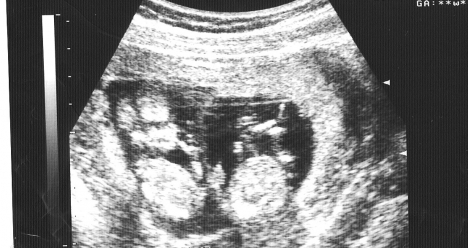

Моя беременность в 2013 году.

В 2013 году я беременею. После задержки мой ХГЧ очень высокий. На УЗИ врач подтверждает, что у меня двойня. Беременность проходит хорошо, мой живот растёт очень быстро. В 2014 году я рожаю двух здоровых и красивых малышей.